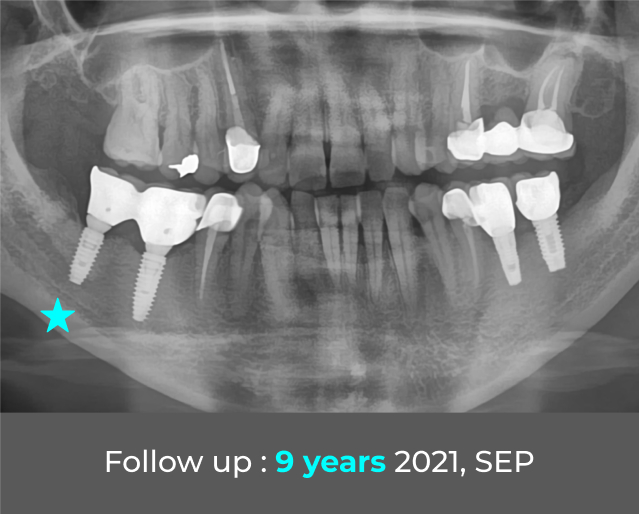

G·DIFF种植体拥有超过8年的长期临床数据,证实其稳定性与天然牙齿相当。全球已售出超过1,000K颗颗种植体。